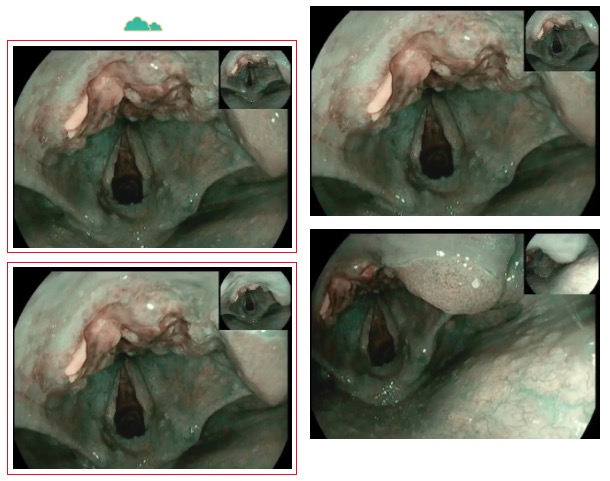

走進(jìn)6診,是一位71歲急診檢查的患者,患者胃內(nèi)大量食物潴留,視野欠清,胃竇及幽門(mén)見(jiàn)一不規(guī)則環(huán)形腫物,腫物表面污穢不平,管腔狹窄,內(nèi)鏡無(wú)法通過(guò),胃竇前壁見(jiàn)約1.5*1.2cm丘狀隆起,中央凹陷。內(nèi)鏡醫(yī)生陳大夫給予病理活檢,待病理結(jié)果出來(lái)行進(jìn)一步治療。

走進(jìn)7診,是一位76歲懷疑胃癌伴幽門(mén)不全梗阻的患者,同樣在胃竇、幽門(mén)處見(jiàn)環(huán)形不規(guī)則隆起腫物致幽門(mén)狹窄,鏡身無(wú)法通過(guò)。